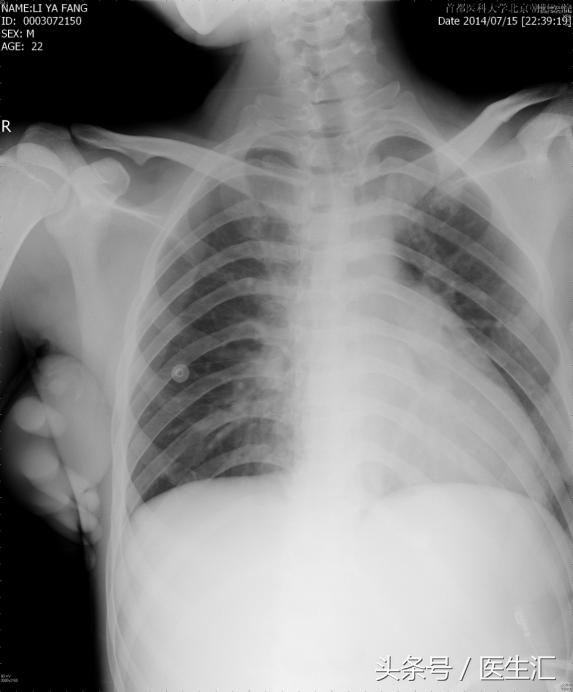

胸片如图